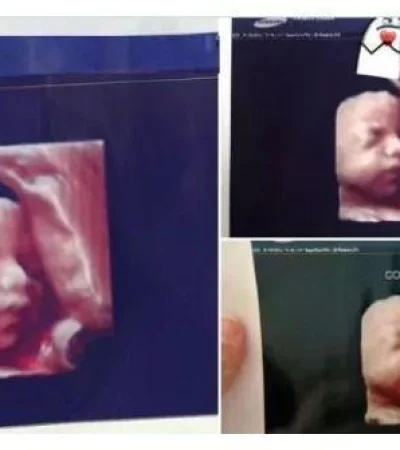

Embarazadas y madres de la ciudad de Formosa, denunciaron a través de las redes sociales que una clínica privada de la capital provincial realizaba (supuestamente) ecografías 5D y les daban las mismas imágenes a todas sus clientas.

Todo comenzó cuando una futura madre compartió en las redes sociales la foto del que creía era su bebé, y uno de sus contactos le respondió que era su futuro hijo, ya que contaba con la misma imagen.

En la red social Twitter siguieron apareciendo madres a quienes le dieron la misma imagen en la ecografía de sus hijos.

Una usuaria confirmó que ya son tres las madres que tienen la misma foto, sin embargo, siguen apareciendo casos.